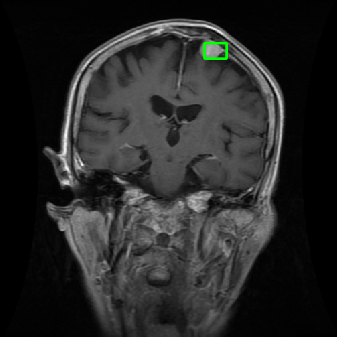

From the above discussions, we have discovered the significant potential of applying Retinex theory to image segmentation and explored its fundamental differences from traditional models. Traditional image segmentation models typically focus on the impact of intensity information on the segmentation results. Therefore, when faced with complex segmentation scenarios, the segmentation results are often affected by lighting, artifacts, and unclear boundaries in the image. As shown in Fig. 1, we present the results of the classical local model LIF [ZHANG20101199] for segmenting brain tumor images along with surrounding tissue edema. The irregular ring-like enhancement caused by the edematous tissue leads to irregular boundaries and low contrast in the images. Consequently, the LIF model can only identify the central necrotic and liquefied regions of the tumor, failing to detect the boundaries and becoming trapped in local minima. In this paper, we draw inspiration from the Retinex theory, which is widely applied in the field of image enhancement. According to Retinex theory, the reflectance component characterizes the intrinsic structural properties of the observed image and preserves texture information independent of illumination variations. By integrating this reflectance component into the level set framework, our model achieves robust segmentation of medical images even under severe intensity inhomogeneity. In addition, a linearized Structural-Prior is proposed to restore intensity consistency and capture local geometric features, thereby improving boundary localization in complex or blurred regions. Furthermore, a relaxed binary level set representation is employed to enhance robustness against noise and to enable accurate tracking of complex contours. Based on these innovations, we propose a novel variational reflectance-based level set model (RefLSM) that simultaneously corrects bias fields and performs segmentation. Experimental results demonstrate that RefLSM significantly outperforms conventional level set methods in both segmentation accuracy and robustness. We present the results of our model segmenting the two brain tumor images mentioned above in Fig. 2.

To address the challenge of segmenting images with severe intensity inhomogeneity, we propose a linearized structural prior that directly operates on the reflectance component . Reflectance-based structural information is more robust to illumination variations and bias field distortions, helping preserve weak edges and subtle anatomical boundaries. As shown in Fig. 2, our method can accurately delineate tumor boundaries and surrounding edema even under severe inhomogeneity, where traditional intensity-based models often fail. The proposed prior aligns smoothed reflectance gradients with data-driven directions, enhancing inter-region contrast, preserving weak edges, and stabilizing the evolution of . Formally, we define the linear structure operator as the gradient field of the smoothed reflectance: